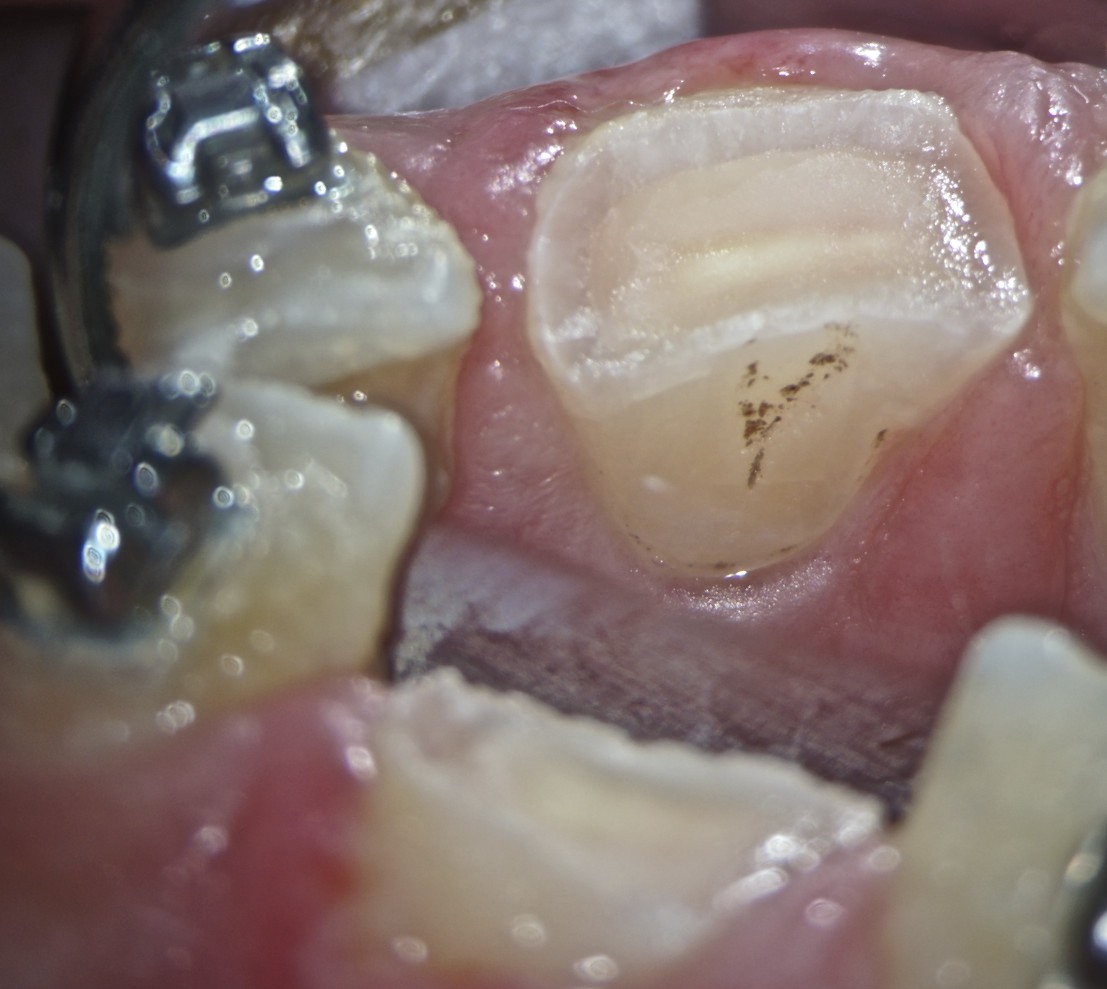

Sorr 01 Veröffentlicht 29. Juni 2014 am 1107 × 989 in Mal wieder Glück gehabt klinische Ausgangssituation